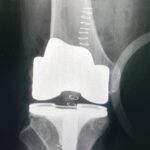

KNEE SURGERY

Our Knee Surgery Service provides treatment for the full spectrum of knee injuries and disorders.

• Arthritis